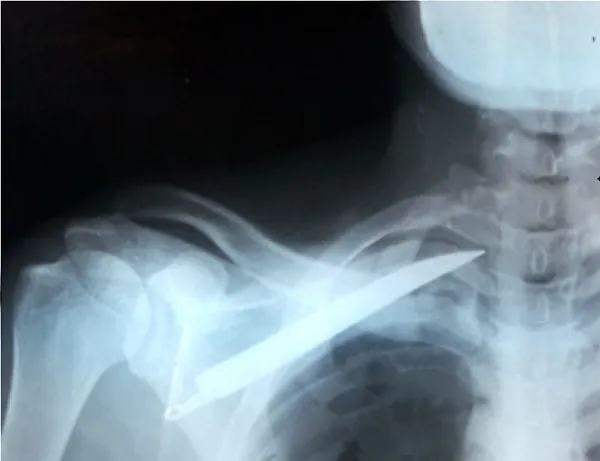

Un joven de 21 años llegó ayer miércoles a la tarde alrededor de las 17hs, al Hospital de la localidad de Pichanal, con un cuchillo incrustado en la espalda pidiendo ayuda.

Se supo que personal policial procedió a la detención de la acusada de 19 años y pareja del damnificado, quien habría agredido al joven con el cuchillo que agarró de la mesa, cuando le reclamaba "el porqué se estaba viendo" con otra mujer, causándole la herida cortopunzante en el omoplato izquierdo.

En el hospital local, la víctima recibió atención médica inicial y la extracción del cuchillo, antes de ser derivado a la Ciudad de Orán para evaluaciones más detalladas.

Personal de la Salud del Hospital Dr Vicente Arroyabe de Pichanal, confirmó que el damnificado ingresó a cirugía debido a la gravedad de la herida. Posteriormente, la hermana de la víctima se presentó en el nosocomio y expresó radicaría la denuncia correspondiente en la dependencia policial.

En el Hospital San Vicente de Paúl en Orán informó que se asistió al joven, diagnosticando una "Herida de Arma Blanca en tórax", por la cual fue suturado y permanece bajo observación.